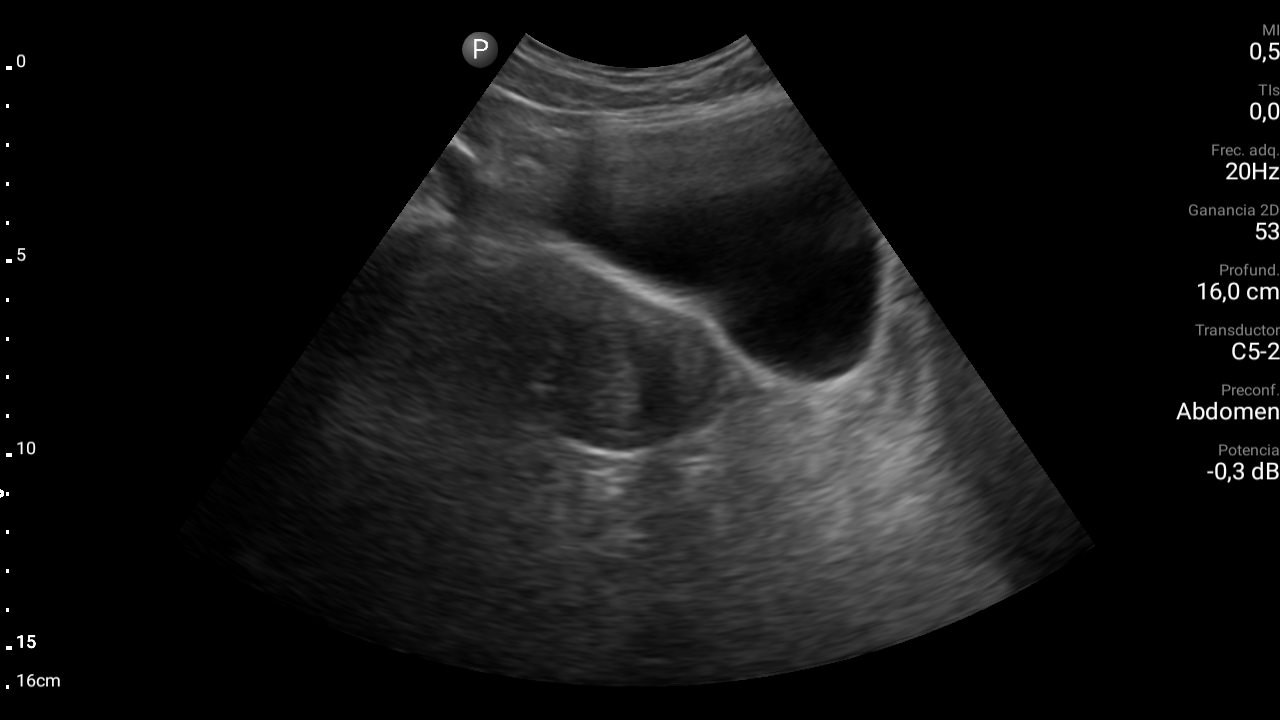

Ecografía abdominal: se observa masa hipoecoica dependiente de útero por lo que se remite de forma preferente a ginecología.

• Ecografía transvaginal: masa uterina compatible con mioma uterino.

Diagnóstico: mioma uterino.